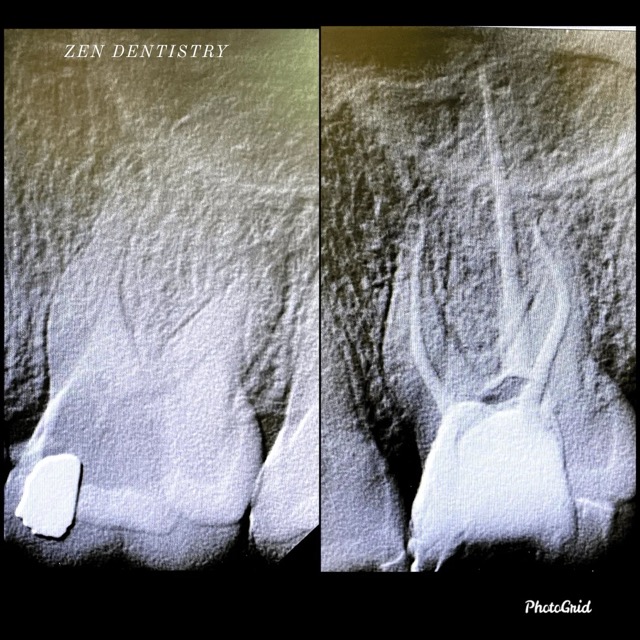

Patient presented to the office with a concern that the tooth has been causing severe constant pain that would become worse at night time. A detailed clinical exams including endodontic screening and x rays let to the diagnosis of irreversible pulpitis (infected nerve) due to gross dental caries that reached the nerve of the tooth with asymptomatic apical periodontitis (normal ligaments).

Root Canal treatment was performed that included removing the caries, dead nerve tissue and disinfecting the canals with proper medication to achieve a 3D hermetic seal of the canals to save the tooth.